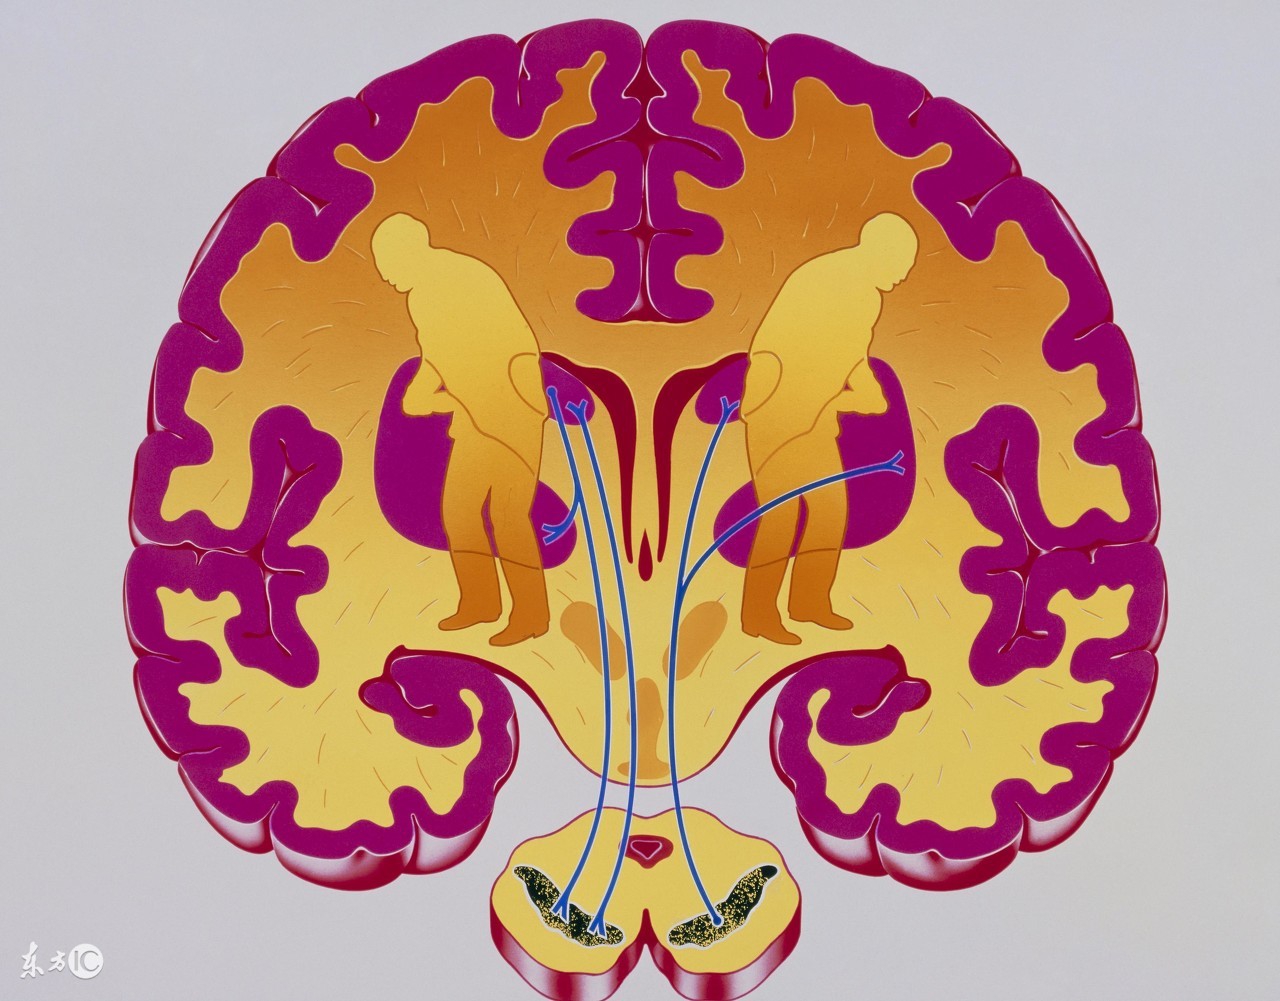

新生儿缺血缺氧性脑病主要见于有严重窒息的足月新生儿,均有明显的宫内窘迫史。由于宫内缺血缺氧影响胎儿脑细胞的能量供给。脑的能量来源和其他器官不同,几乎全部由葡萄糖氧化而来。新生儿脑的代谢最旺盛,脑的能量占全身氧能量的一半,但脑内糖原很少,而葡萄糖及氧全靠血液供给,故缺血缺氧首先影响脑的代谢。